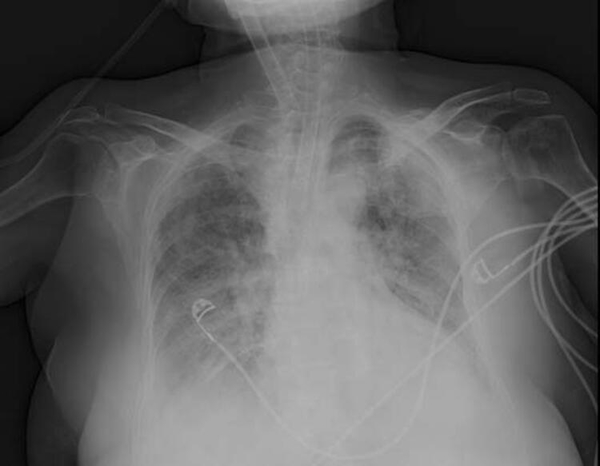

Anadolu Ajansı (AA) Ankara Şehir Hastanesinde Kovid-19 tedavisi gören hastalara ait akciğer görüntülerine ulaştı. Görüntülerde, hastalığın ne kadar hızlı ilerlediği ve akciğerleri nasıl tuttuğu ortaya çıktı.

Prof. Dr. Karalezli, koronavirüs tedavisi gören hastalara ait akciğer görüntülerinden hastalığın yol açtığı tahribatı ve hastalar üzerindeki etkileri anlattı.

Normal akciğer görüntüleri ile koronavirüs hastalarının akciğer görüntüleri arasında ciddi farklar bulunduğunu belirten Karalezli, şu bilgileri verdi:

"İnsanların aradaki farkları anlamaları için her iki akciğer görüntülerine de yer verdim. Görüntülerdeki beyazlıklar akciğerdeki tutulumu gösteren görüntüler ne yazık ki. Bu hastalar yoğun bakım hastaları. Filmler birbirine az çok benzeyen şekilde. Altta yatan hastalığı olanlarda ise daha kötü seyrediyor."

Kliniğe yeni başvuran bir hastanın, 5 Ağustos'ta çekilen tomografi görüntülerindeki tipik koronavirüs görüntülerinin olduğunu ifade eden Karalezli, hastanın bir hafta içerisindeki tomografi görüntüsünde ciddi değişiklik olduğunu ve enfeksiyonun çok arttığını söyledi.